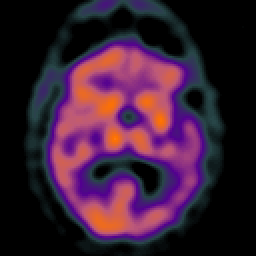

Subdural Hygroma,overlay -- Slice #25

[Home][Help][Clinical] Slice 25